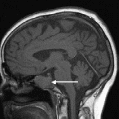

Магнитно-резонансная томография. Наиболее информативный метод исследования гипофиза. При магнитно-резонансной томографии визуализируются передняя и задняя доли, воронка гипофиза, возможно оценить симметричность гипофиза, положение воронки, состояние спинки турецкого седла. На МР-сканах структура аденогипофиза гомогенная, изоинтенсивна с белым веществом мозга.

Аденомы гипофиза на Т1 ВИ – визуализируются как зоны со сниженным по сравнению с остальной тканью аденогипофиза сигналом, на Т2ВИ – как зоны с повышенным сигналом. При внутривенном контрастировании аденомы накапливают контрастное вещество и можно более детально оценить структуру опухоли.

Рисунок Магнитно-резонансная томограмма головного мозга в сагиттальной плоскости. Микроаденома.